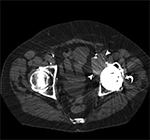

Small Particle Disease. Axial CT image of the pelvis demonstrates left total hip arthroplasty with adjacent cortical disruption (curved arrow) and destructive soft tissue lesion (arrowheads) arising from the anteromedial aspect of the acetabulum, consistent with small particle disease due to polyethylene wear.